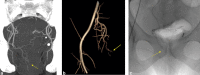

Emborrhoid: Rectal Artery Embolization for Hemorrhoid Disease

- Vidal V, Louis G, Bartoli J M, Sielezneff I. Embolization of the hemorrhoidal arteries (the emborrhoid technique): a new concept and challenge for interventional radiology. Diagn Interv Imaging. 2014;95(03):307–315. - PubMed

- Vidal V, Sapoval M, Sielezneff Y. Emborrhoid: a new concept for the treatment of hemorrhoids with arterial embolization: the first 14 cases. Cardiovasc Intervent Radiol. 2015;38(01):72–78. - PubMed